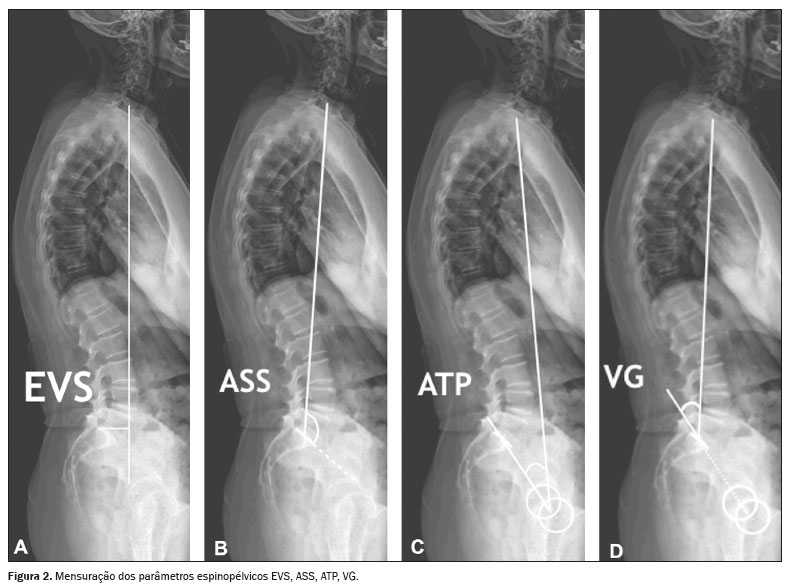

Para mensurar os parâmetros espinopélvicos e ângulos das curvaturas vertebrais foi utilizado o software Surgimap (Nemaris Inc., New York, NY, EUA). Os seguintes parâmetros foram avaliados: inclinação sacral (IS); versão pélvica (VP); incidência pélvica (IP); lordose lombar (LL); cifose torácica (CT); eixo vertical sagital (EVS); ângulo espinossacral (ASS); ângulo T1 pélvico (ATP) e versão global (VG), conforme mostrado nas Figuras 1 e 2. A IS corresponde ao ângulo formado entre a placa da extremidade superior de S1 e a linha horizontal. A VP corresponde ao ângulo formado entre uma linha vertical que se origina no centro da cabeça femoral e uma linha que parte do centro da cabeça femoral para o ponto médio da placa terminal de S1. A IP corresponde ao ângulo formado pela perpendicular ao platô sacral e a linha que conecta o ponto médio deste com o centro de rotação femoral. A LL é a medida do ângulo de Cobb do platô superior de S1 até o platô superior de L1. A CT é a medida do ângulo de Cobb do platô inferior de T12 até o platô superior de T1. O EVS é a medida da distância horizontal entre a linha de prumo de C7 e a linha vertical que passa pelo ponto posterossuperior de S1. O ASS corresponde ao ângulo formado entre a linha que passa do centro de C7 ao centro da placa terminal de S1 e a superfície da placa terminal sacral. O ATP é o ângulo obtido por uma linha formada do centro geométrico das cabeças femorais ao centro do corpo vertebral T1 e uma linha do centro geométrico das cabeças femorais ao centro da placa terminal superior de S1. A VG é definida como o ângulo formado por uma linha do centro da placa final superior sacral ao centro do corpo vertebral C7 e uma linha do centro geométrico das cabeças femorais ao centro da placa terminal sacral(15). Os contornos das cabeças femorais foram marcados e foram traçadas linhas adjacentes ao platô superior de S1, platô superior de L1, platô inferior de T12, platô superior de T1 e platô inferior de C2. A partir dessas marcações, o software calculou automaticamente os parâmetros espinopélvicos e as curvaturas vertebrais.